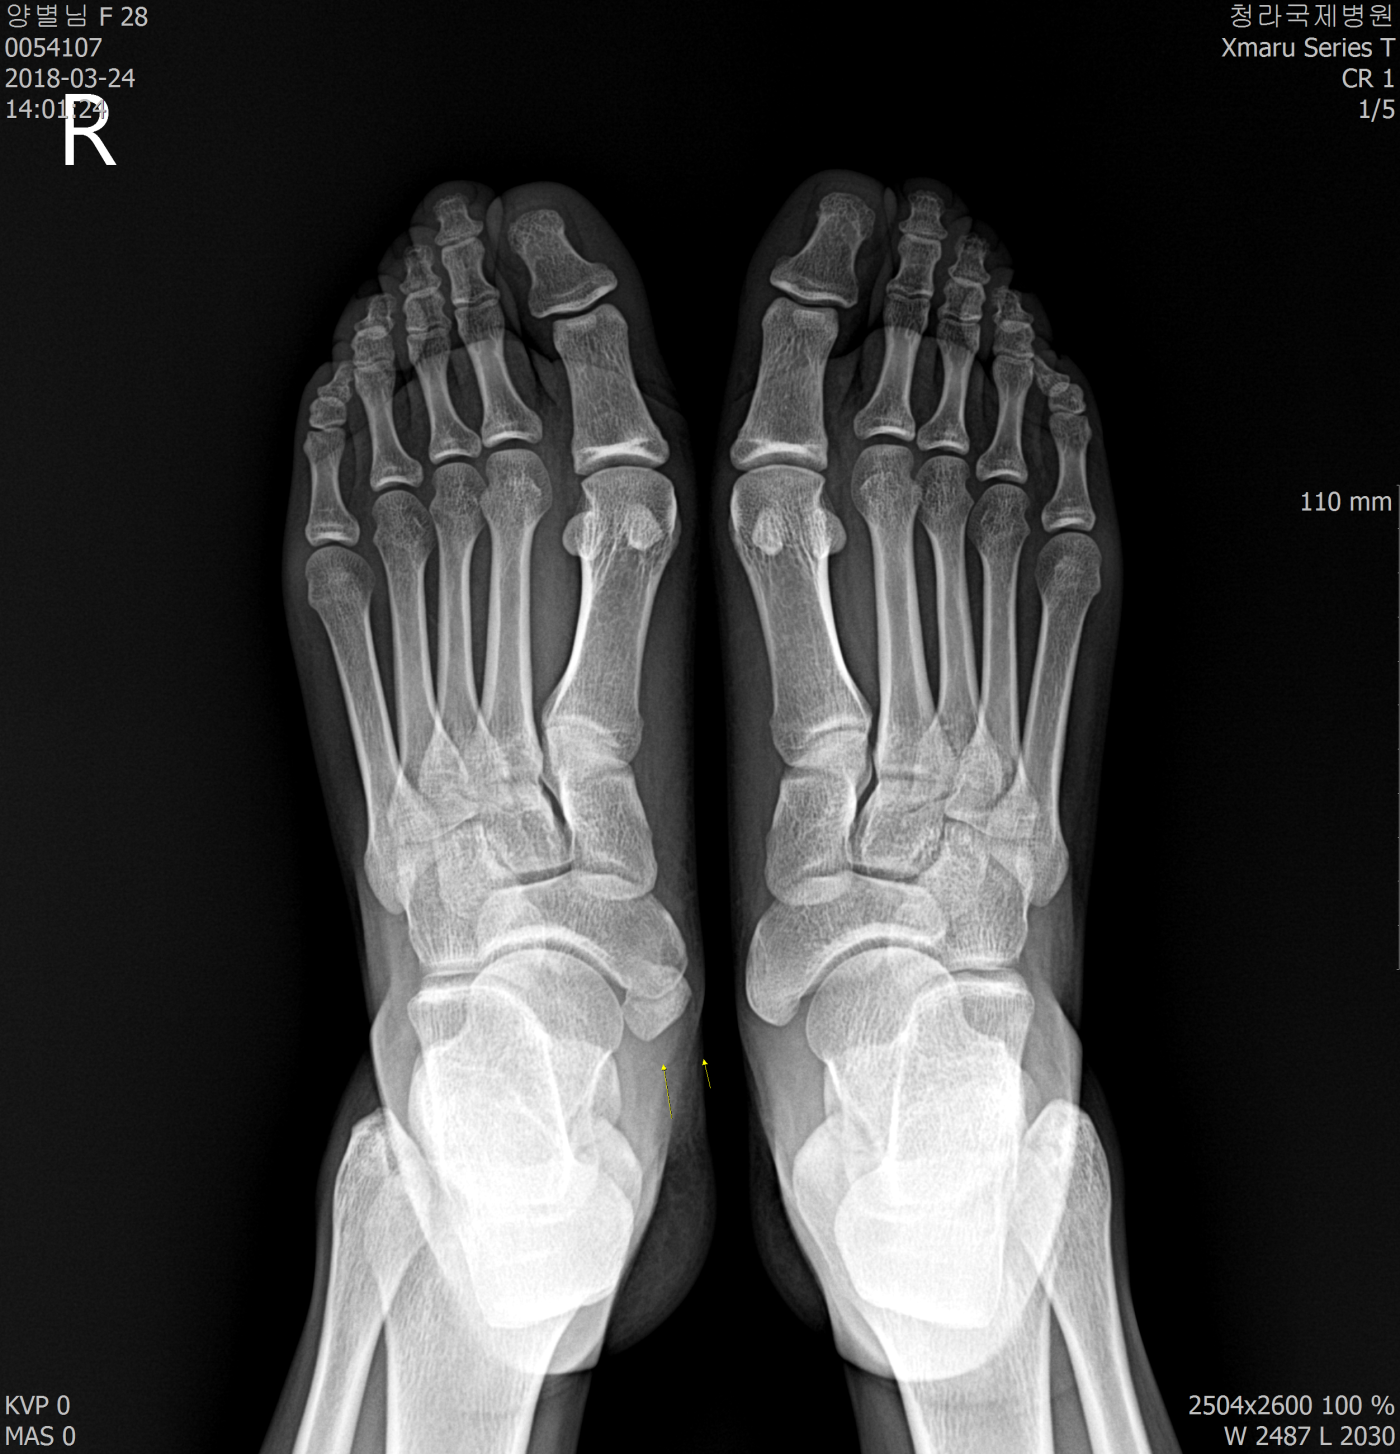

족부

부주상골

부주상골로 통증이 있습니다.

수술말고 보존적 치료원하는데

깔창 제작 가능할까요?